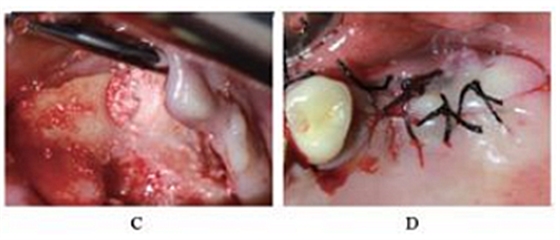

术后5个月,患者无流涕、鼻塞,无其他自觉症状。CBCT示:左侧鼻甲基本恢复正常,上颌窦高密度影较前明显减少,仍有少量黏膜增厚。26牙RBH8.1mm,27牙RBH8.4mm(图4)。拟26~28牙种植修复。

图4 种植前CBCT。注:A,矢状面;B,26颊舌向切面;C,27颊舌向切面;D,28颊舌向切面。